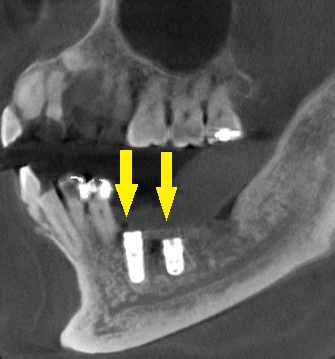

3か月ほどして、CTを撮影してみると、下の写真2段目のように、大きく骨欠損となっていました。

2本のインプラント埋入を目指したいのですが、2本目の部位では、下方に通っている神経までの距離は3~4mm程度でした。

ショートインプラントでも厳しいので、この場合は、人工骨を用いて、上方に骨を増やす手術を併用する計画としました。